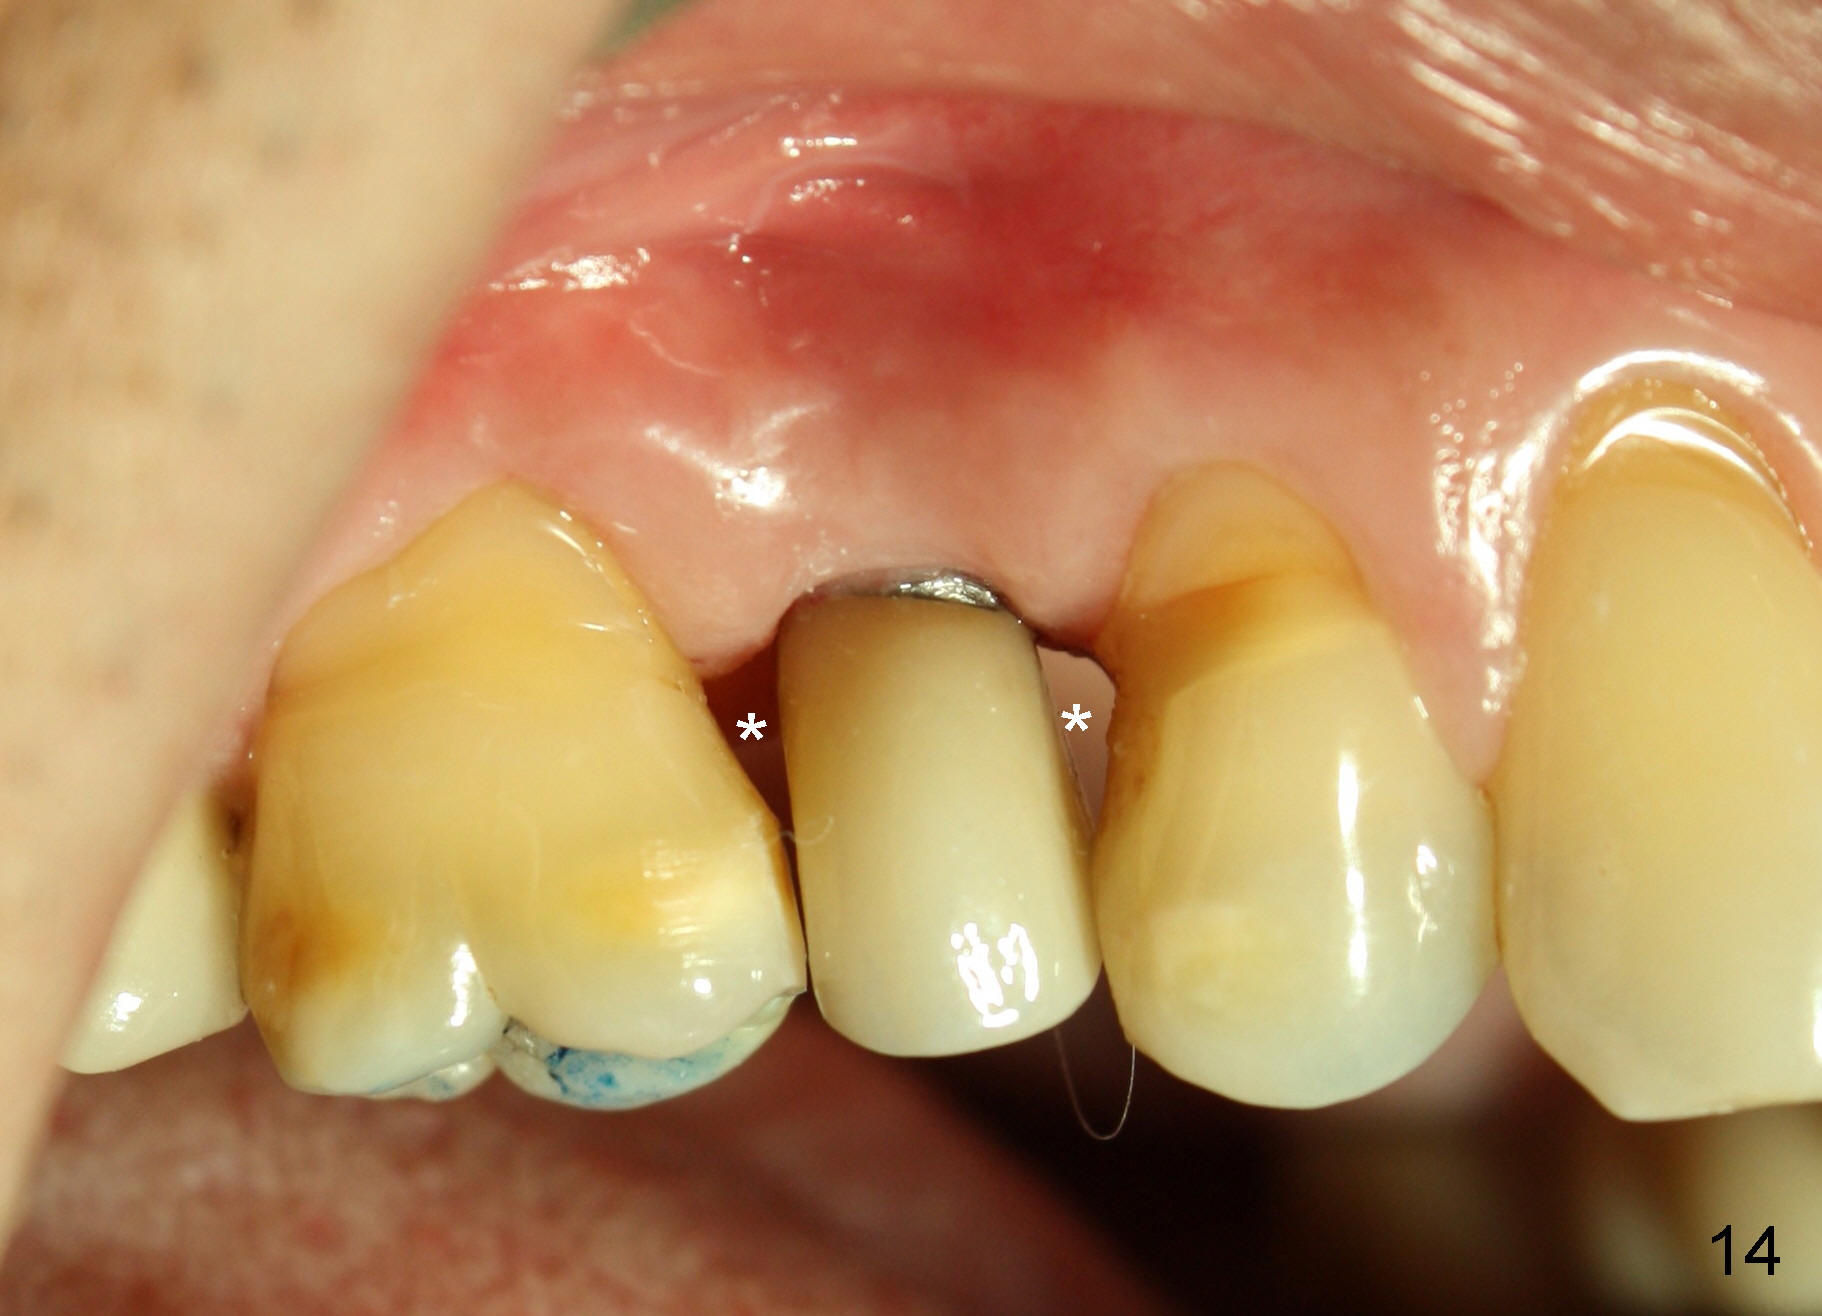

X-ray at 2.5 months postop shows crestal bone loss (Fig.12 *), although the implant is stable without inflammation (Fig.13 C: healing cuff). When the crown is bonded 3.5 months postop, there is no papilla (Fig.14 *).